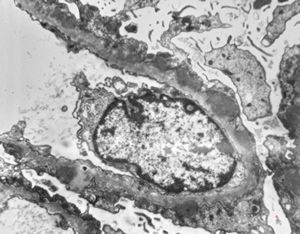

F,2y. | normal kidney

M,13y. | thin basement membrane syndrome